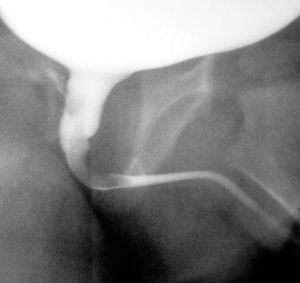

La ecografía renal y vesical muestra distensión vesical, sin hidronefrosis, litiasis, ni otros hallazgos patológicos. Ante la recurrencia del proceso se solicita cistografía miccional que demuestra la existencia a la altura de la uretra posterior de una lesión ocupante de espacio, exofítica, polipoidea que se inicia en el verum montanum, se extiende distalmente y obstruye de manera parcial la uretra (figs. 1 y 2).

Figura 1.CUMS: Fase miccional. Defecto de repleción a nivel de uretra prostática que causa disminución de la luz uretral.

Figura 2. Defecto de repleción, alargado, con base en la pared posterior de la uretra prostática (verum montanum) y que se proyecta hacia la uretra bulbar.

El diagnóstico se basa en la cistouretrografía miccional seriada (CUMS), en la cual se puede ver un defecto de repleción ovalado y móvil, de contornos lisos y bien circunscritos, que puede ocupar uretra prostática o cuello vesical1.